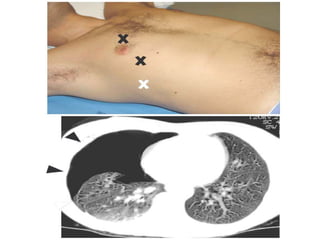

• 43.

Notice the increasedlucency of the cardiophrenic sulci in this patient with inferior anteromedial pneumothoraces. A CT scan confirms the diagnosis

• 44.

 a hyperlucentupper quadrant with visualization of the superior surface of the diaphragm and visualization of the inferiorvena cava.  double-diaphragm sign

• 45.

 Antero lateralair may increase the radiolucency at the costo phrenicsulcus. This is called the deep sulcus sign.

• 46.

 Apicolateral pneumothorax (arrows) withright upper lobe collapse (arrowheads)

• 47.

 shifting ofthe heart border,  the superior vena cava, and the inferior vena cava.  The shifting of these structures can lead to decreased venous return.

• 48.

•Mediastinal shifT is usually seenin a tension pneumothorax. •The most reliable sign of tension pneumothorax is depression of a hemidiaphragm.